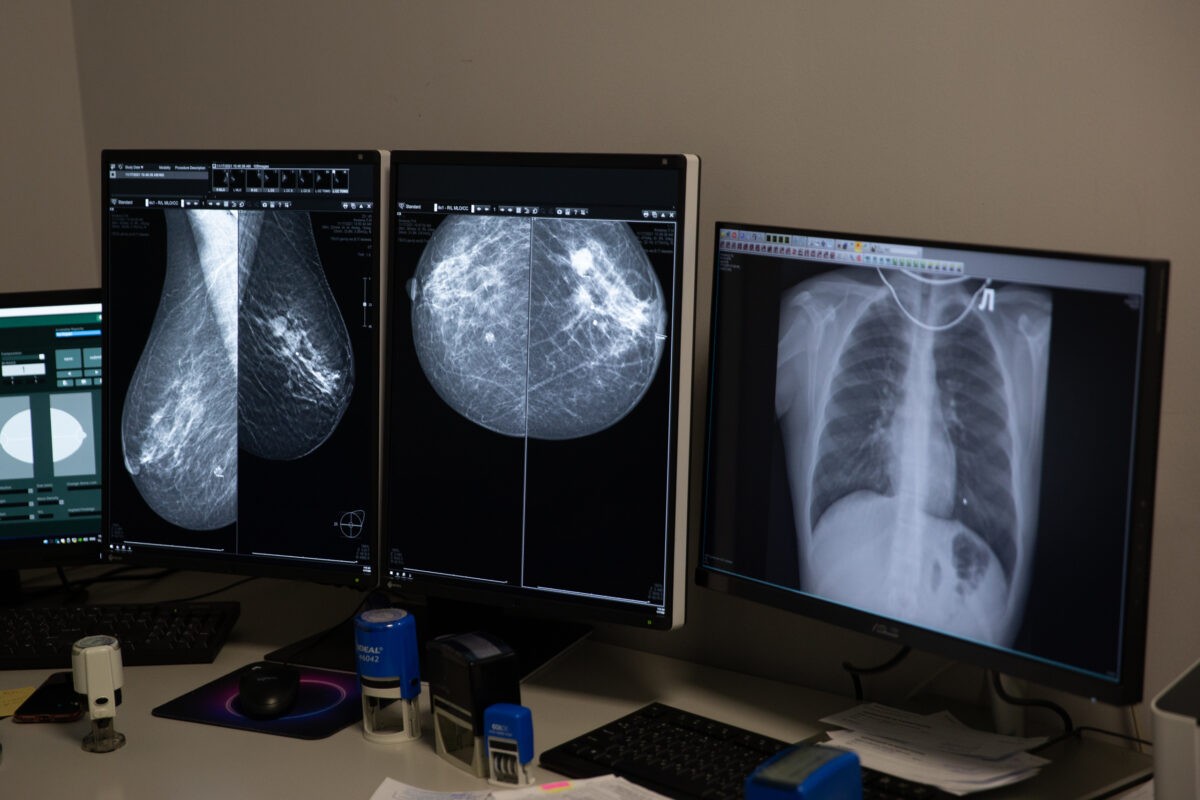

Низкодозная КТ позволяет выявить опухоли размером больше 1-2 миллиметров. Еще один метод для выявления рака легких – бронхоскопия. Его применяют, если у пациента наблюдается стойкий кашель, выделение мокроты, крови или других примесей, а также тогда, когда рентген или КТ-снимки дают повод заподозрить в легких образование.